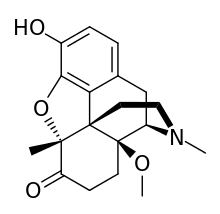

Structures of Morphine family

| Morphine family | ||||

|---|---|---|---|---|

14-Hydroxymorphine 14-Hydroxymorphine |

2,4-Dinitrophenylmorphine 2,4-Dinitrophenylmorphine |

6-Methyldihydromorphine 6-Methyldihydromorphine |

6-Methylenedihydrodesoxymorphine 6-Methylenedihydrodesoxymorphine |

6-Acetyldihydromorphine hydrochloride 6-Acetyldihydromorphine hydrochloride |

Azidomorphine Azidomorphine |

Chlornaltrexamine Chlornaltrexamine |

Chloroxymorphamine Chloroxymorphamine |

Desomorphine Desomorphine (Dihydrodesoxymorphine) |

Dihydromorphine Dihydromorphine |

Ethyldihydromorphine Ethyldihydromorphine |

Hydromorphinol Hydromorphinol |

Methyldesorphine Methyldesorphine |

N-Phenethylnormorphine N-Phenethylnormorphine |

6-nicotinoyldihydromorphine 6-nicotinoyldihydromorphine |

RAM-378 RAM-378 | ||||